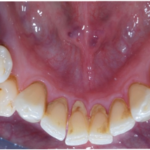

Fig. 2C-2F Fotografie intraorali palatali e linguali